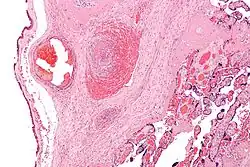

| Intermediate magnification micrograph of the placental disc showing a thrombosed fetal vein, as may be seen in fetal thrombotic vasculopathy. H&E stain. | |

It can be diagnosed by histomorphologic examination of the placenta and is characterized by fetal vessel thrombosis and clustered fibrotic chorionic villi without blood vessels.

Low mag.

Low mag. -